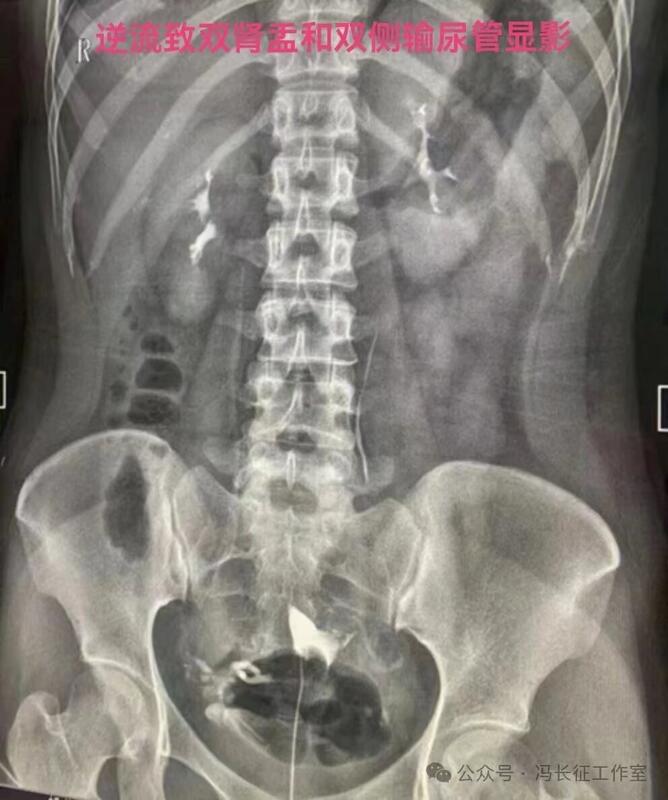

在子宫输卵管造影,用碘油做造影剂当出现逆流时立即停止造影检查,避免更多碘油进入静脉造成肺栓塞是正确的。但是,当用的造影剂是碘水时,出现逆流时还是可以继续进行造影检查,最终完成造影检查,尽量给被检查者一个完整的检查。千万不要听所谓的砖家乱讲,当发现有造影剂进入间质或血管,应立即停止造影。我们大家都知道成人在做CT增强检查时,常规用高压注射器直接从静脉注入约100毫升含碘水剂进行检查几十年了,因此,碘水是可以进入静脉和淋巴的。一般子宫输卵管造影所用含碘水剂20毫升左右,即使20毫升含碘水剂都逆流静脉不会对身体有啥影响的。因为含碘水剂主要经肾从尿液排出体外,有时还相当于免费送一个静脉肾盂造影检查。

造影剂逆流可以进入静脉和淋巴管,逆流分三种:(1)淋巴逆流;(2)静脉逆流;(3)淋巴和静脉混合性逆流。其实,一般多是静脉和淋巴都有的混合性逆流,淋巴逆流是造影当时以淋巴逆流为主,同时有少量的静脉逆流,本来淋巴管后来就是要汇入到静脉的。静脉逆流也是以静脉逆流为主,同时有少量的淋巴逆流。